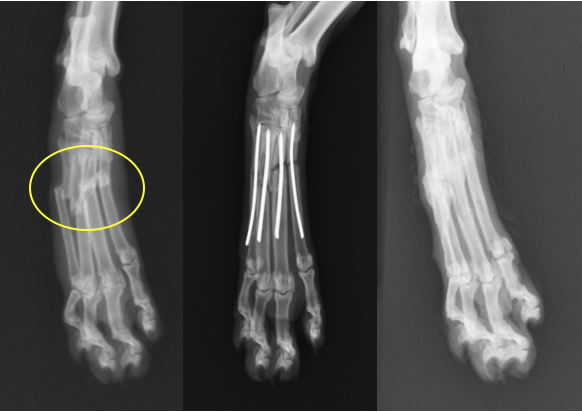

猫の手根関節の脱臼と中手骨骨折 淀川中央動物病院